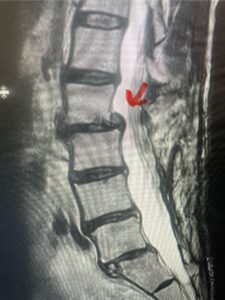

Fig. 9a Sagittal T2-weighted cervical MRI demonstrating severe upper cervical spinal cord compression secondary to C2 anterior subluxation on C3 with development of thickened posterior degenerative material (red arrow)

Fig. 9b